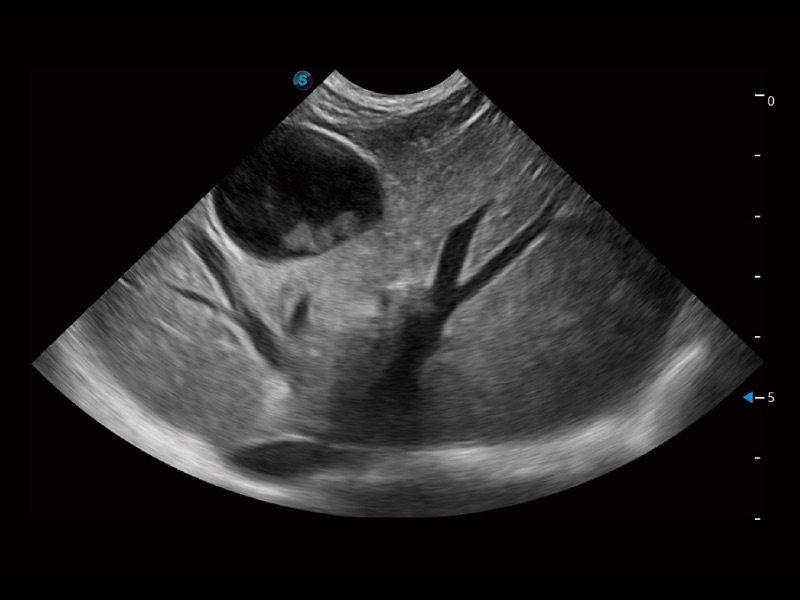

增强穿刺针在动物解剖结构中的位置,提高穿刺介入的安全性和准确性。

操作简便,无需高频度外力作用即可真实反映组织的形变,快速评估肿瘤良恶性。

ProPet 70专为动物医生设计,对不同的动物体型和生理结构作出了针对性的优化。通过动物影像专用软件,可满足个性化的应用需求,帮助动物医生获得更精确的诊断数据。